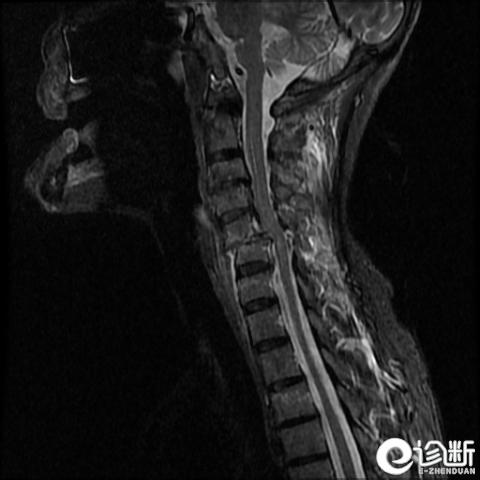

颈椎骨折

MRI:评估软组织

轴向压缩(最常见的机制)导致爆裂骨折

屈曲/牵张损伤导致脱位

神经损伤罕见(特别是C1及C2骨折)